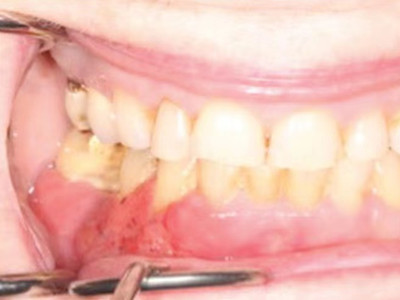

牙龈癌多源于牙间乳头及龈缘区,溃疡呈表浅、淡红,以后可出现增生。由于黏骨膜与牙槽突附着甚紧,较易早期侵犯牙槽突骨膜及骨质,进而出现牙松动,并可发生脱落。X线片可出现恶性肿瘤的破坏特征虫蚀状不规则吸收。

牙龈癌常发生继发感染,肿瘤伴以坏死组织,触之易出血。体积过大时可出现面部肿胀,浸润皮肤。